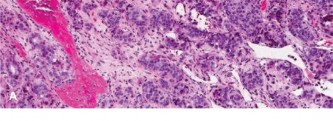

Histopathological analysis of the core samples revealed highly pleomorphic spindle cells producing disorganized, lace-like osteoid matrix. Frequent atypical mitotic figures, areas of coagulative necrosis, and hyperchromatic nuclei were observed. Immunohistochemistry was positive for SATB2 and negative for cytokeratins and S100, confirming the diagnosis of high-grade conventional osteosarcoma (osteoblastic subtype).